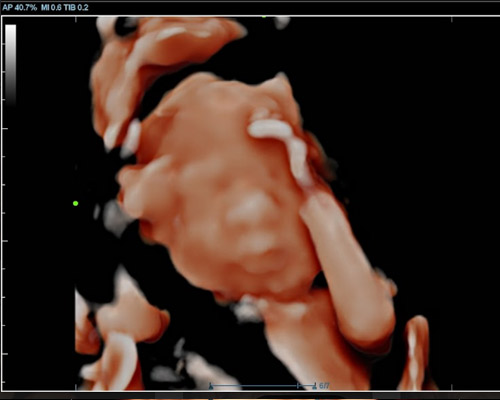

- See your baby’s face clearly using HD Live imaging

- Watch natural movements and expressions

- Capture detailed images to keep

Our 3D/4D Bonding Scan is a truly special experience, allowing you to connect with your baby like never before. Using advanced HD Live technology, you can enjoy clear images and even catch glimpses of facial expressions.

Our Scans